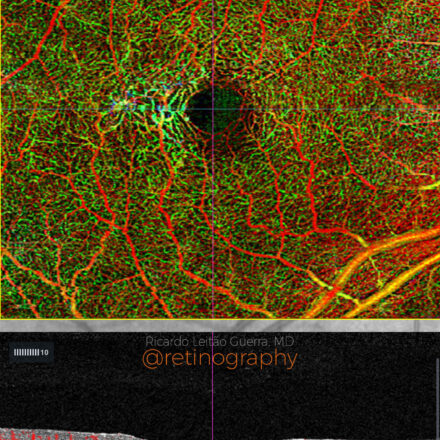

MacTel type 2

55yo

55yo In macular telangiectasia type 2 (MacTel), the OCTA depth-enhanced map improves visualization of vascular alterations across different retinal layers. It highlights capillary rarefaction and telangiectatic vessels, particularly in the deep capillary plexus and outer retina. This tool enhances diagnostic accuracy and monitoring of neovascular complications in MacTel. #MacTel #OCTA #DepthEnhancedMap […]